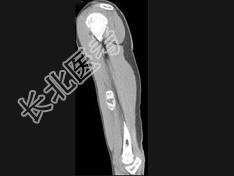

- 单项选择题男,21岁, 左上肢有外伤史,现感局部疼痛, 可扪及包块,结合图像, 最可能的诊断是 ( )

A、骨外骨肉瘤

B、骨外软骨肉瘤

C、皮质旁骨肉瘤

D、邻皮质软骨瘤

E、骨化性肌炎